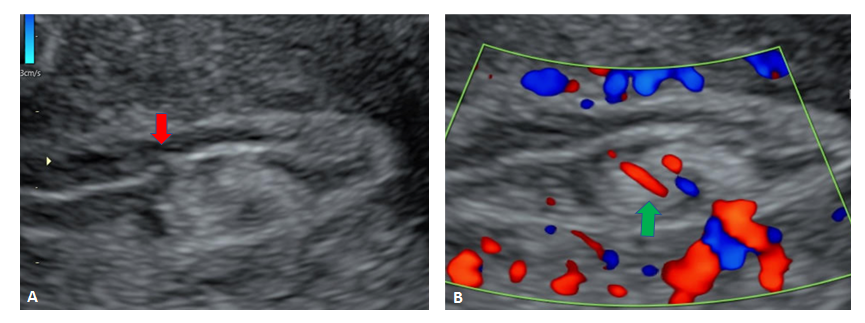

We report a case of a 24-year-old lady who was unable to conceive for a period of 8 years. Infertility workup was negative. In 2018, she conceived, however cardiac activity was not demonstrated in the fetus and eventually medical abortion was performed. Transvaginal sonography was performed for the same at a private center which did not pick up any uterine structural abnormality. In 2021, the patient presented to our emergency department with a 14-week gestation pregnancy with complaints of bleeding per vaginum for 2 days. Antenatal transvaginal ultrasound was performed for confirmation and viability of an intrauterine pregnancy. An intrauterine gestational sac with crown rump length corresponding to 8 weeks 5 days and absent cardiac activity was seen suggesting the diagnosis of missed abortion (Figure 1). Surrounding the gestational sac was fluid with internal echoes suggesting failure of implantation (Figure 2). A well-defined uniformly echogenic pedunculated lesion was seen in the endometrial cavity (Figure 3). As it was traced towards the point of its origin, a focally hypoechoic region was demonstrated interrupting the hyperechoic endometrial lining (Figure 4), classically described as the ‘interrupted mucosa sign’ [2]. On colour doppler image, a single vascular pedicle was demonstrated (Figure 5), known as the ‘pedicle artery sign’ [3]. Based on these classical features the diagnosis of an endometrial polyp was made. It was seen to abut the gestational sac suggesting mechanical hindrance to growth of the embryo (Figure 6). On real time imaging, the endometrial polyp was seen prolapsing from towards the uterine fundus to the lower uterine segment (Figure 7). For better characterization of the endometrial polyp, it has been recommended to distend the uterine cavity with saline (also known as saline infusion sonohysterography) [4,5], however in our case it was unwarranted because the gestational sac and fluid naturally distended the uterine cavity and helped in optimum visualization (Figure 4,6). Figure 8 depicts another case of an endometrial polyp showing a non-gravid uterus with an echogenic lesion in the endometrial cavity showing the classical interrupted mucosa sign (Figure 8A) and the feeding artery sign (Figure 8B).

Figure 8: Another case of endometrial polyp showing a non-gravid uterus with an echogenic lesion in the endometrial cavity showing the classical interrupted mucosa sign (Figure 8A, red arrow) and feeding artery sign (Figure 8B, green arrow).